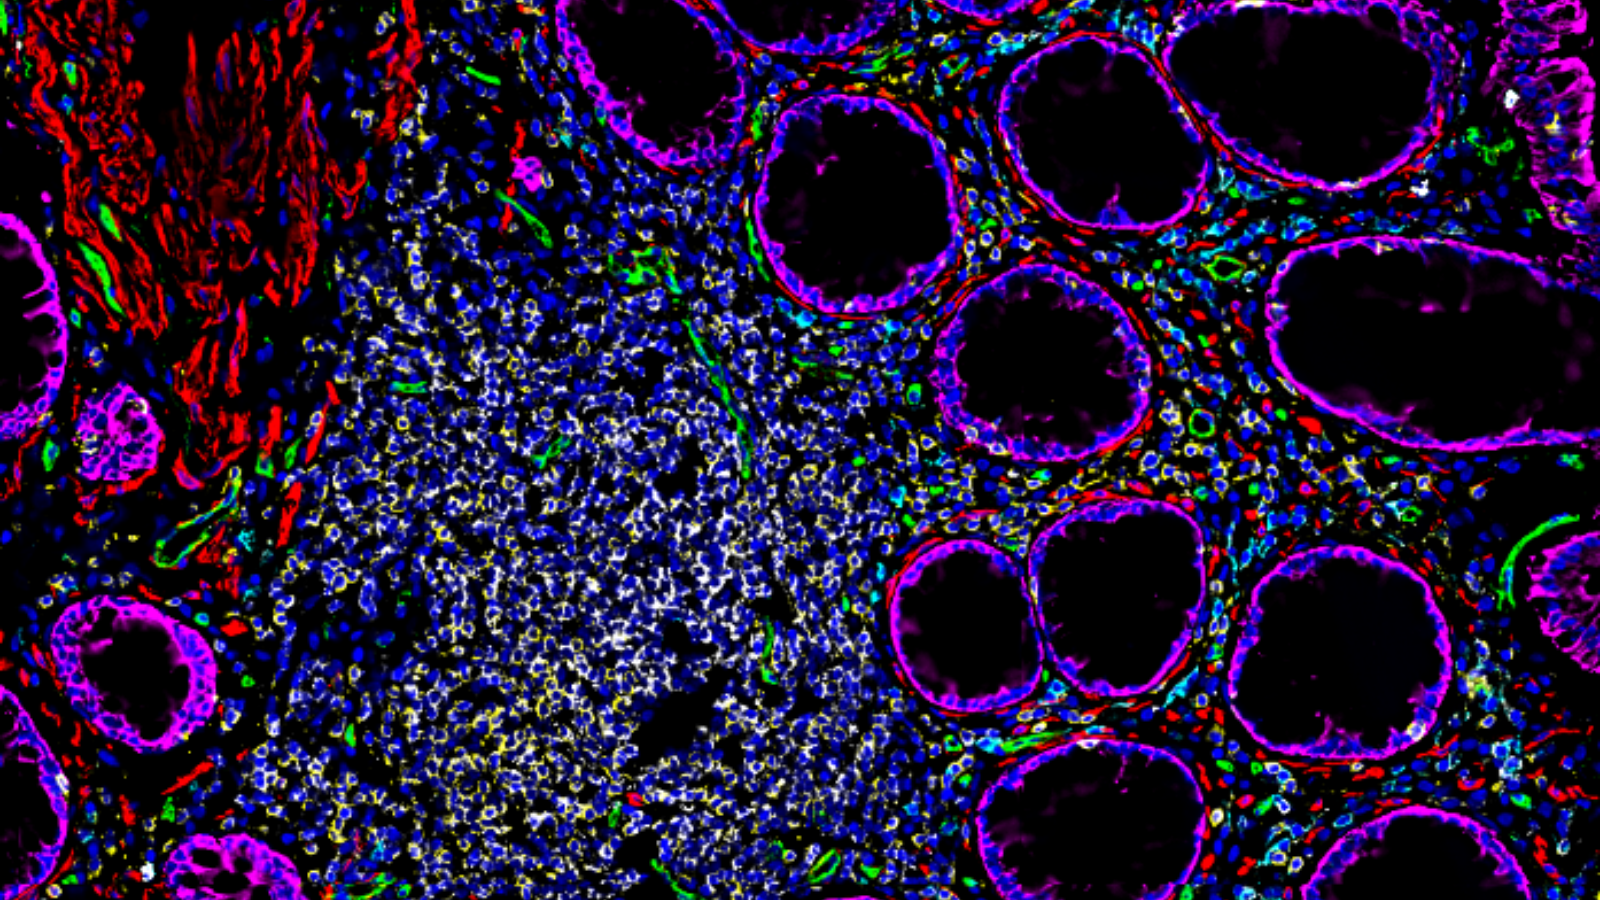

The lining of the uterus & fetal cells within & around maternal spiral arteries, courtesy of Dr. Michael Angelo at Stanford

7 proteins in a section of healthy human colon tissue, courtesy of Dr. John Hickey at Stanford